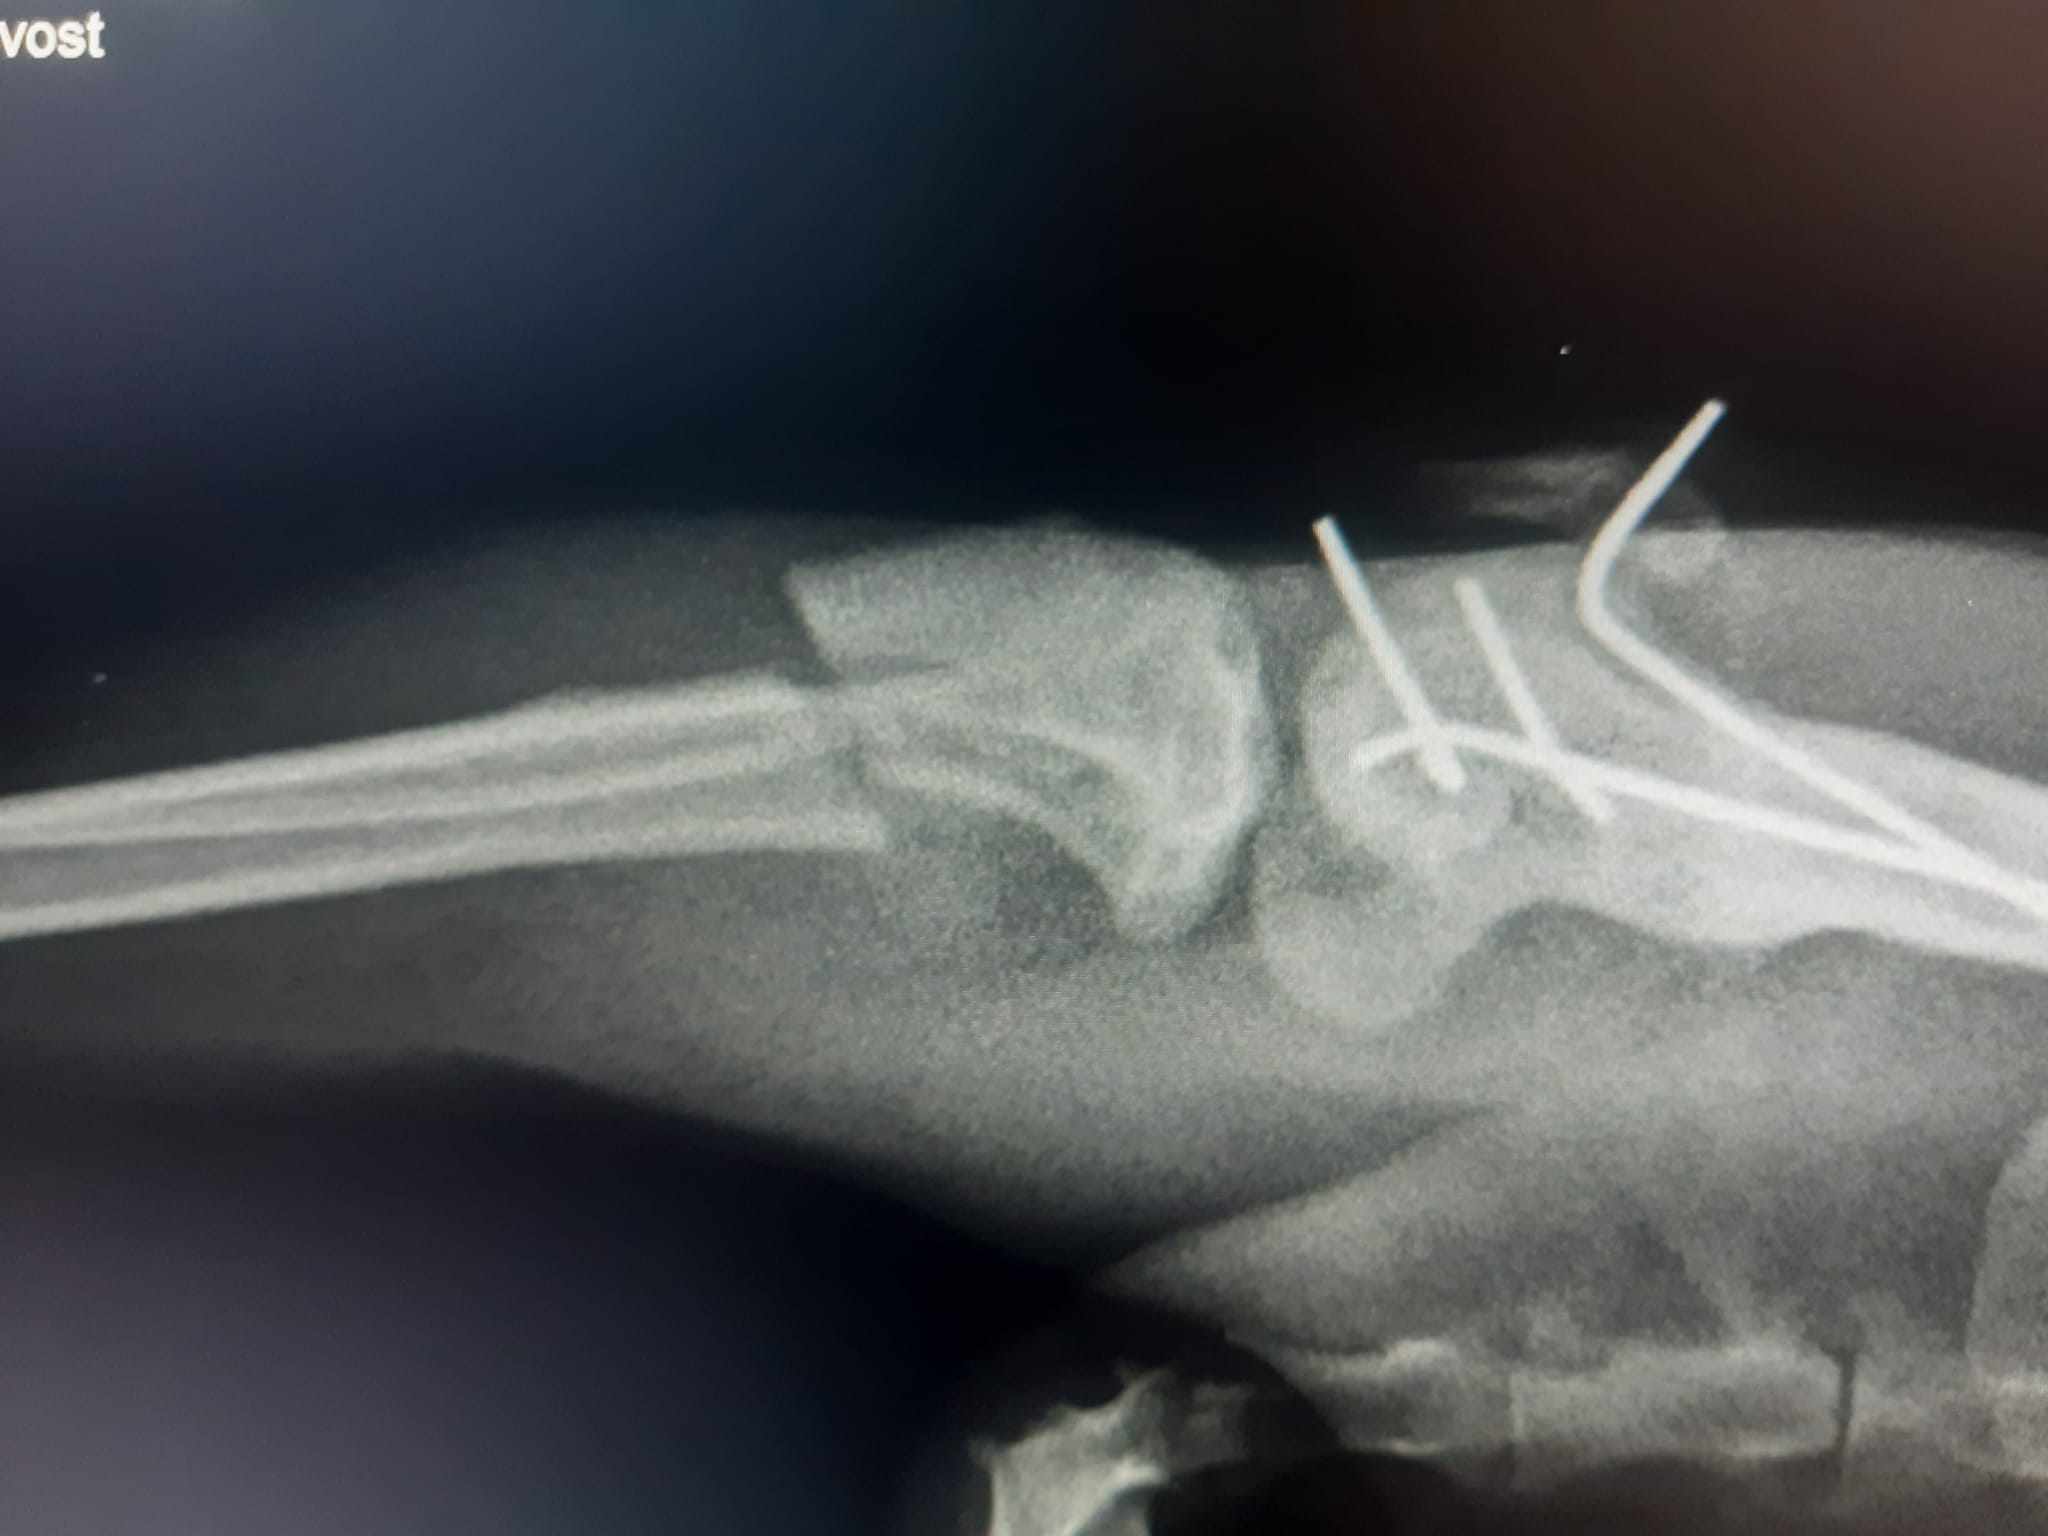

MICKA přišla za jedním pánem do dílny v Prachaticích ve velmi zuboženém stavu, byla podvyživená, hladová a zraněná. Pán se svou ženou se jí ujali, poskytli jí přístřeší a stravu, přičemž se snažili najít původního majitele. Při návštěvě veterinární ordinace se ukázalo, že kočička má zlomeninu pánevní končetiny a že už byla jednou operována, na rentgenu byla viditelná starší zlomenina stehenní kosti fixovaná pomocí drátů. Tentokrát je zlomená stejná nožička pod kolenem.